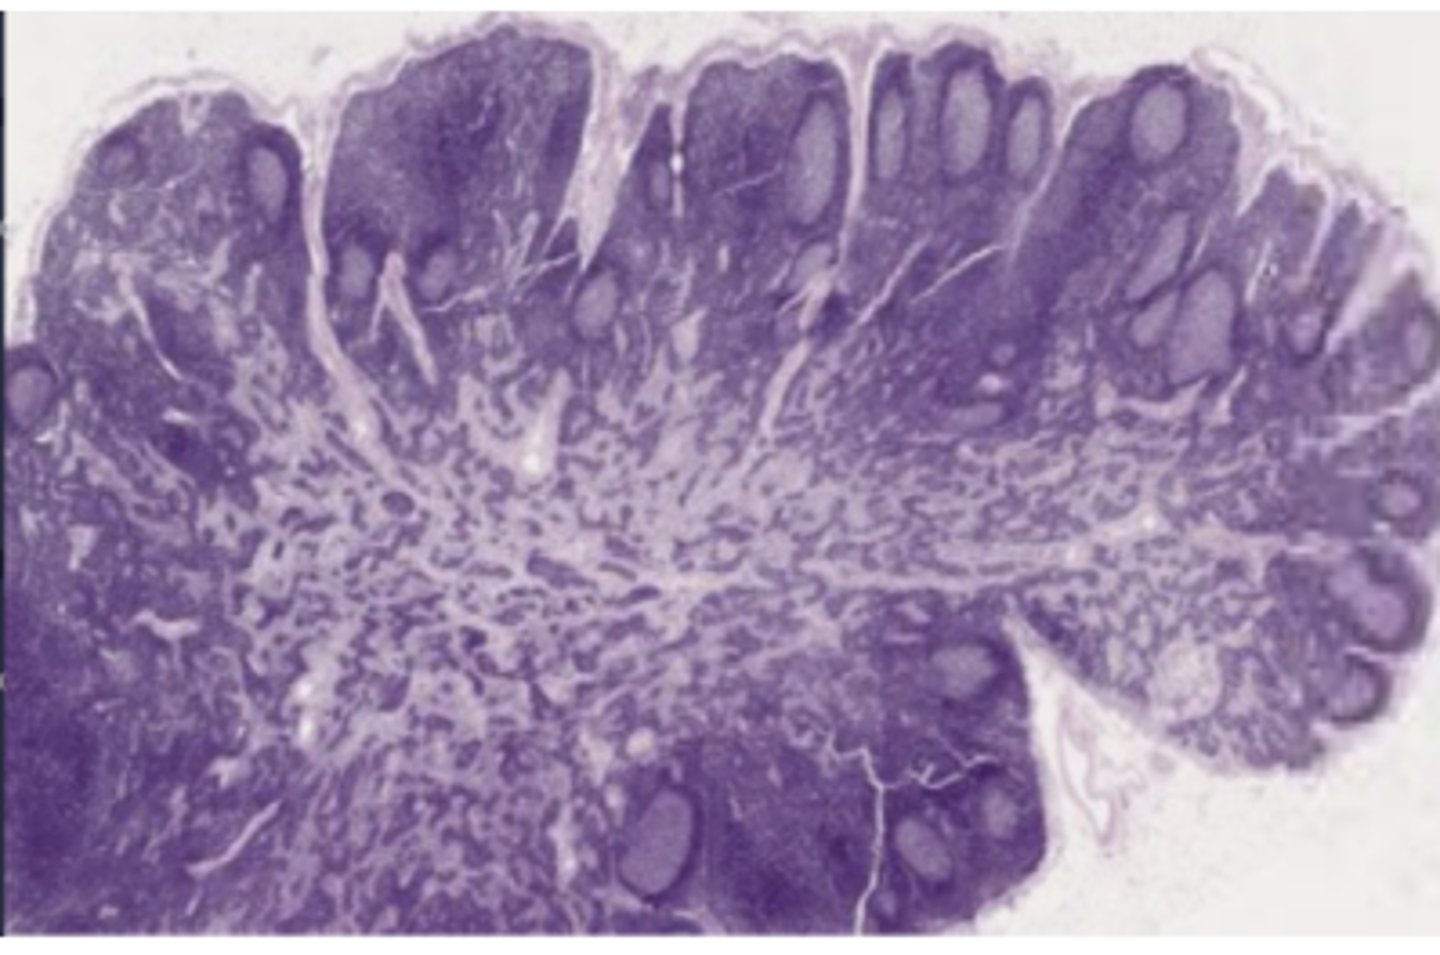

lacks villi

Mucosa of large intestine

appendix